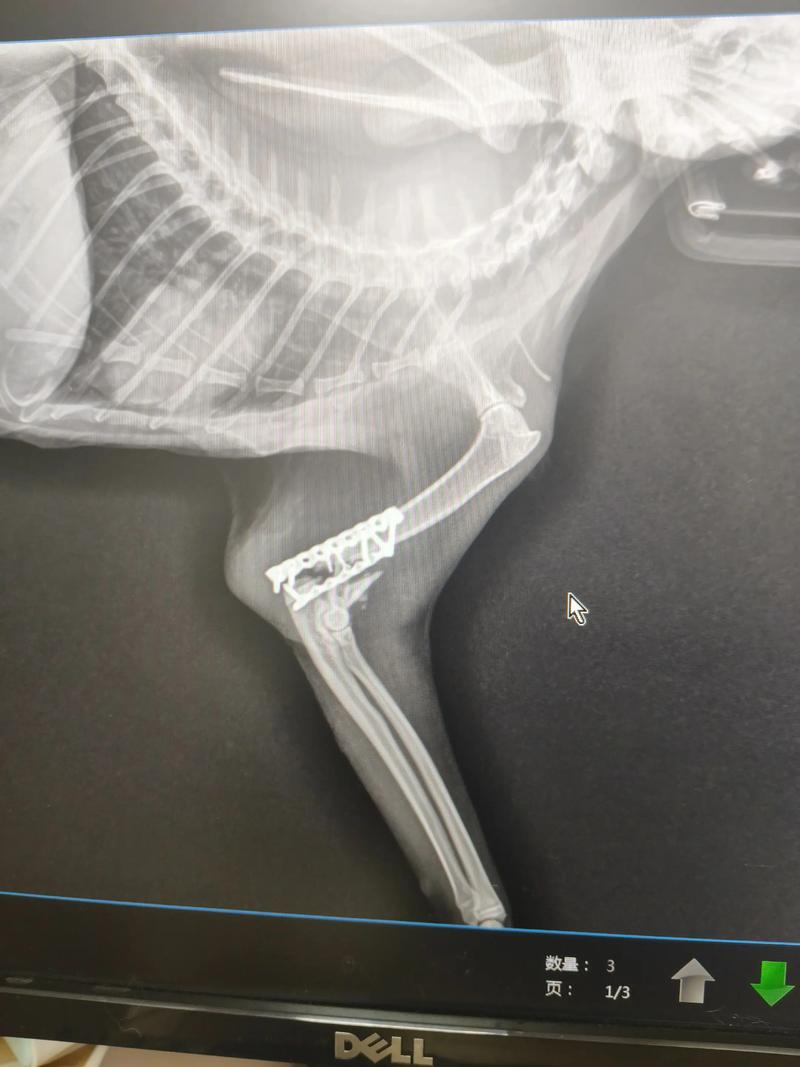

根据X光片显示,猫咪盆骨和股骨头处发生骨折,很难自己自愈,建议及时去医院制定内固定的手术方案,防止因为拖延治疗,导致猫咪出现尿失禁、瘫痪、走路瘸拐等后遗症。

〖Four〗、由于延误时间过久不适合进行手术固定,但是宠物主人为了使猫咪美观不影响以后走路仍然要求就行内固定治疗,再猫咪主人的再三要求下,决定对猫咪进行手术,快速形成的骨痂给手术带来很大的难度,也给猫咪带来了很大的风险。下面 是手术之后的X光图,希望猫咪能够尽快恢复好。